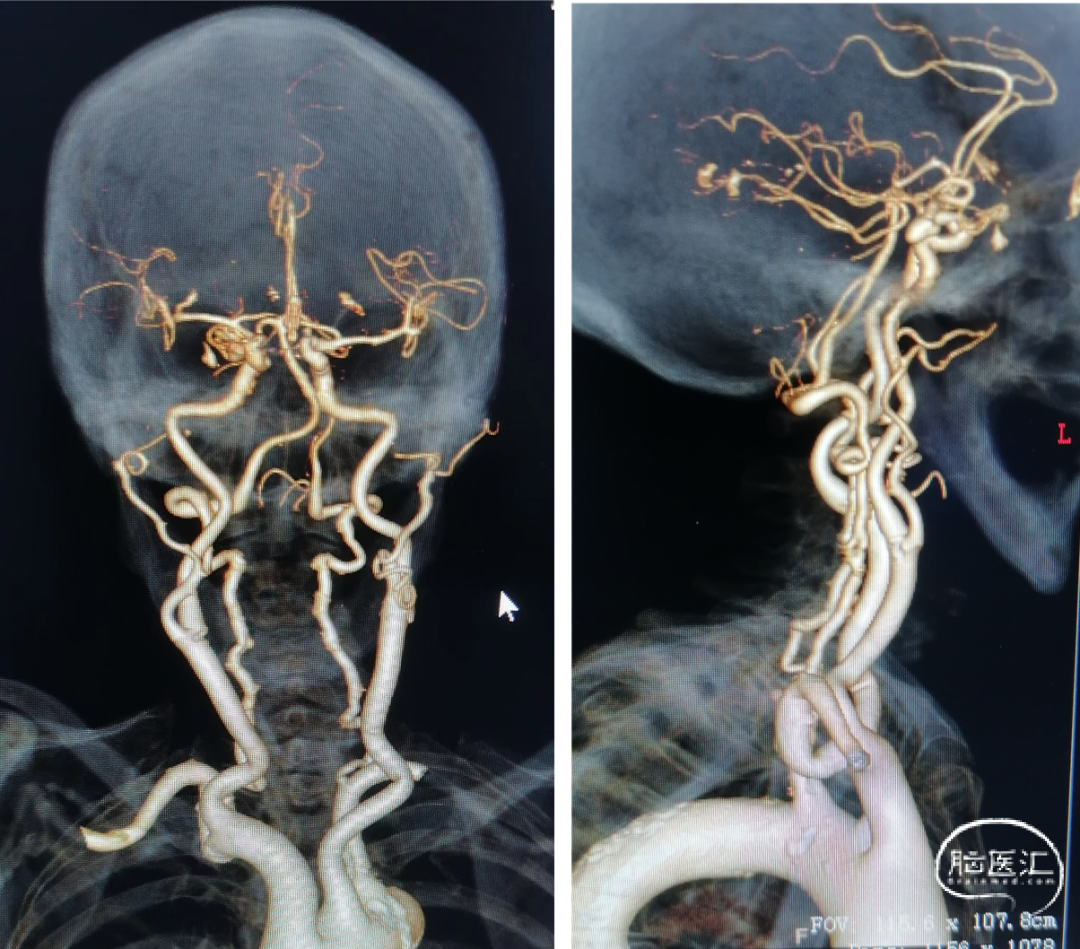

男性患者,75岁。

主诉:头痛1月余。

现病史:患者于1月前体检行CTA检查,提示右侧颈内动脉后交通段动脉瘤。

既往史:高血压、糖尿病史。

查体:入院神经系统查体未见阳性体征。

术前影像学检查:CTA示右侧颈内动脉后交通段动脉瘤。